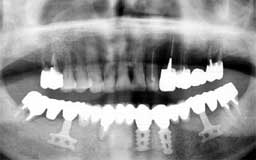

Qさん 初診時 55歳 男性

上顎の歯もかなり末期状態で、このまま放置しておくと下顎同様数年後には全ての歯を失う であろうことが予想されます

歯科治療

Qさん 11年後 66歳

今となっては古いタイプのインプラントですが、残存する下顎歯を最大限に利用してフルマ ウスの補綴処置を行いました。術後のメインテナンスは熱心で追加処置がないまま良好な予 後を保っています。10年間インプラントが機能していることも値打ちですが、何よりも上顎 の歯が1本も失われることなく機能していることに注目してください